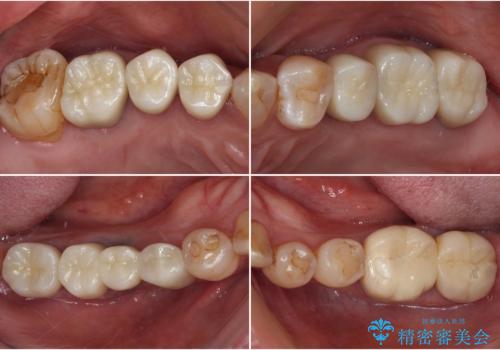

[ インプラントによる機能回復 ] 強い咬合力 放置した虫歯の治療

![[ インプラントによる機能回復 ] 強い咬合力 放置した虫歯の治療の症例 治療前](https://seimitsushinbi.jp/wp/wp-content/uploads/2022/07/dbc5e5b52dd96aeab54aa69e57a96bd1-500x350.jpg?v=1658988380)

![[ インプラントによる機能回復 ] 強い咬合力 放置した虫歯の治療の症例 治療後](https://seimitsushinbi.jp/wp/wp-content/uploads/2022/07/5634e865a3957c7dade18cdc7bf6b192-500x350.jpg?v=1658988421)